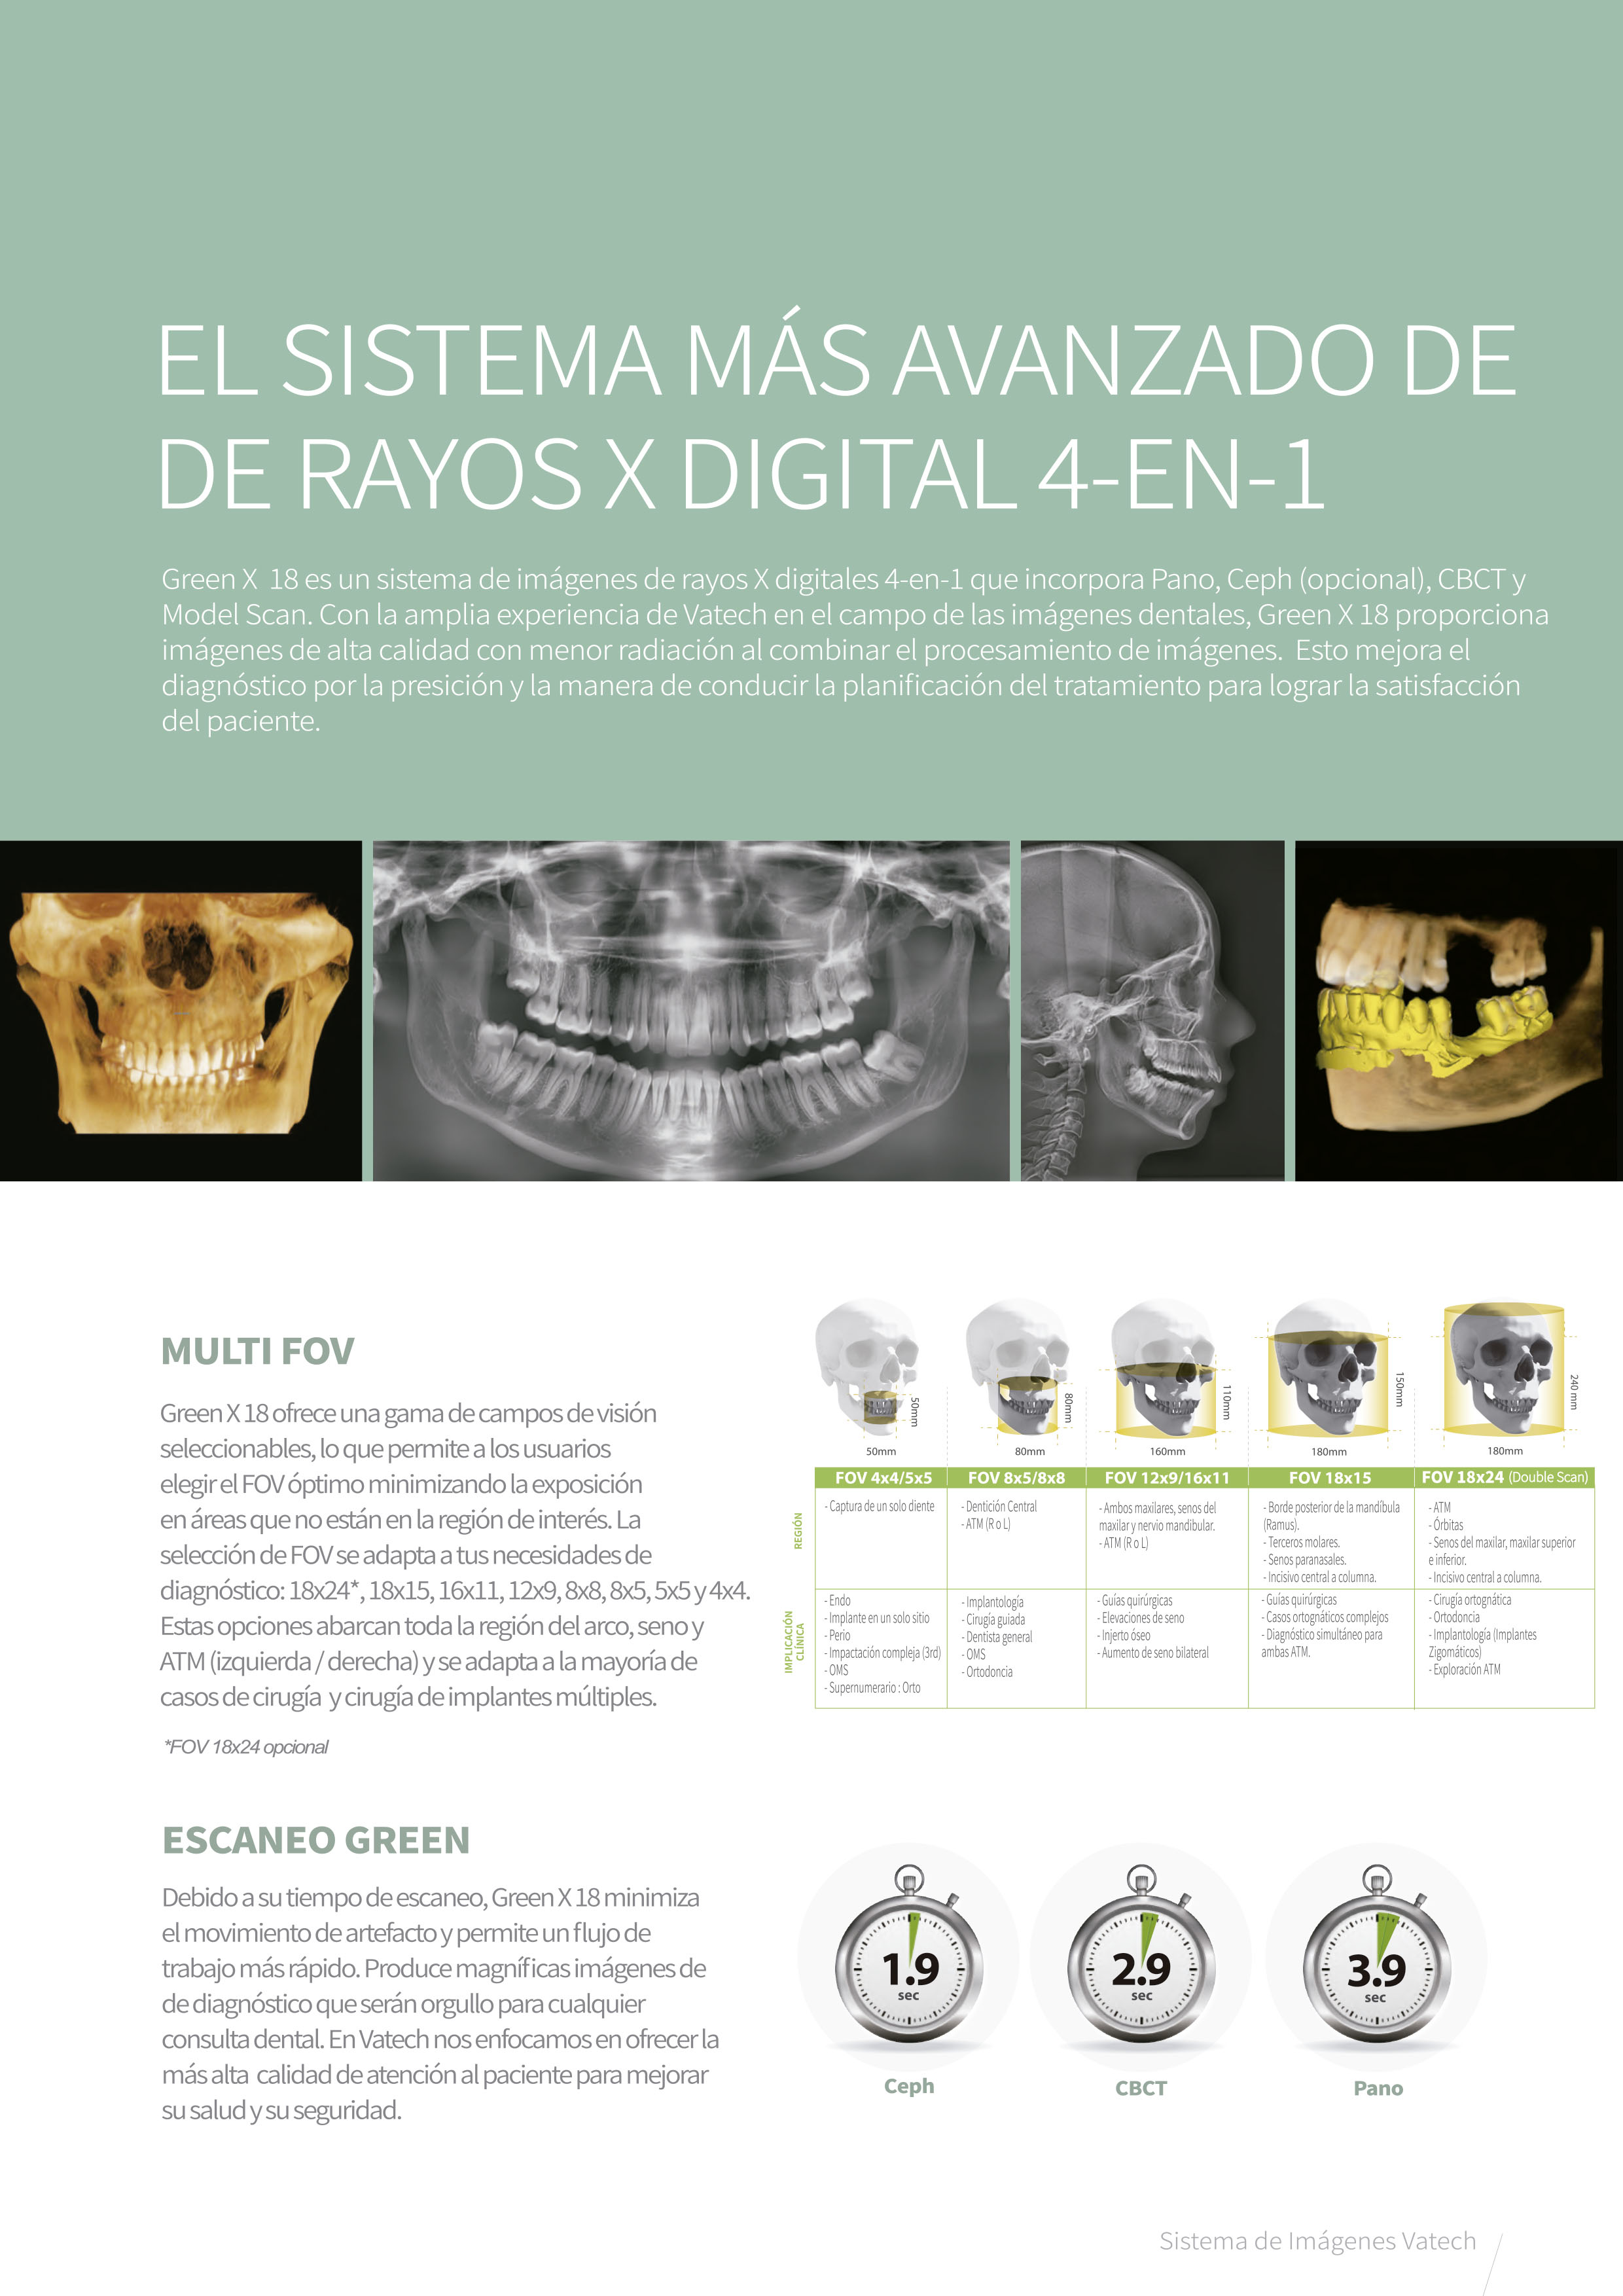

Tomógrafo 3D Dental con Ortopantomógrafo y Cefalostato.

Aplicaciones:

- CBCT, Cone Beam Computer Tomography. Imágenes en 3D de 18 x 24 cm.

- FOV hasta 24 x 15 cm (Double Scan). Sensor 18 x 15 cm.

- Función Insight (Panorámica 2.5 D).

- Escaneo de modelos 3D.

- Escaneo Green.

- Modo ENDO con alta resolución 4 x 4 cm (Voxel de 0.05 mm.).

- Radiografía Panorámica (ortopantomografía).

- Radiografía Lateral de Cráneo (Ceph Rápido de 1. 9 Segundos).

- Radiografía de ATM.

- Radiografía de Senos Paranasales.

- Radiografía de Aleta de Mordida.

- Radiografía Carpal.

- Radiografía AP y PA.

- Radiografía Waters.

- Radiografía Submentovertebral.